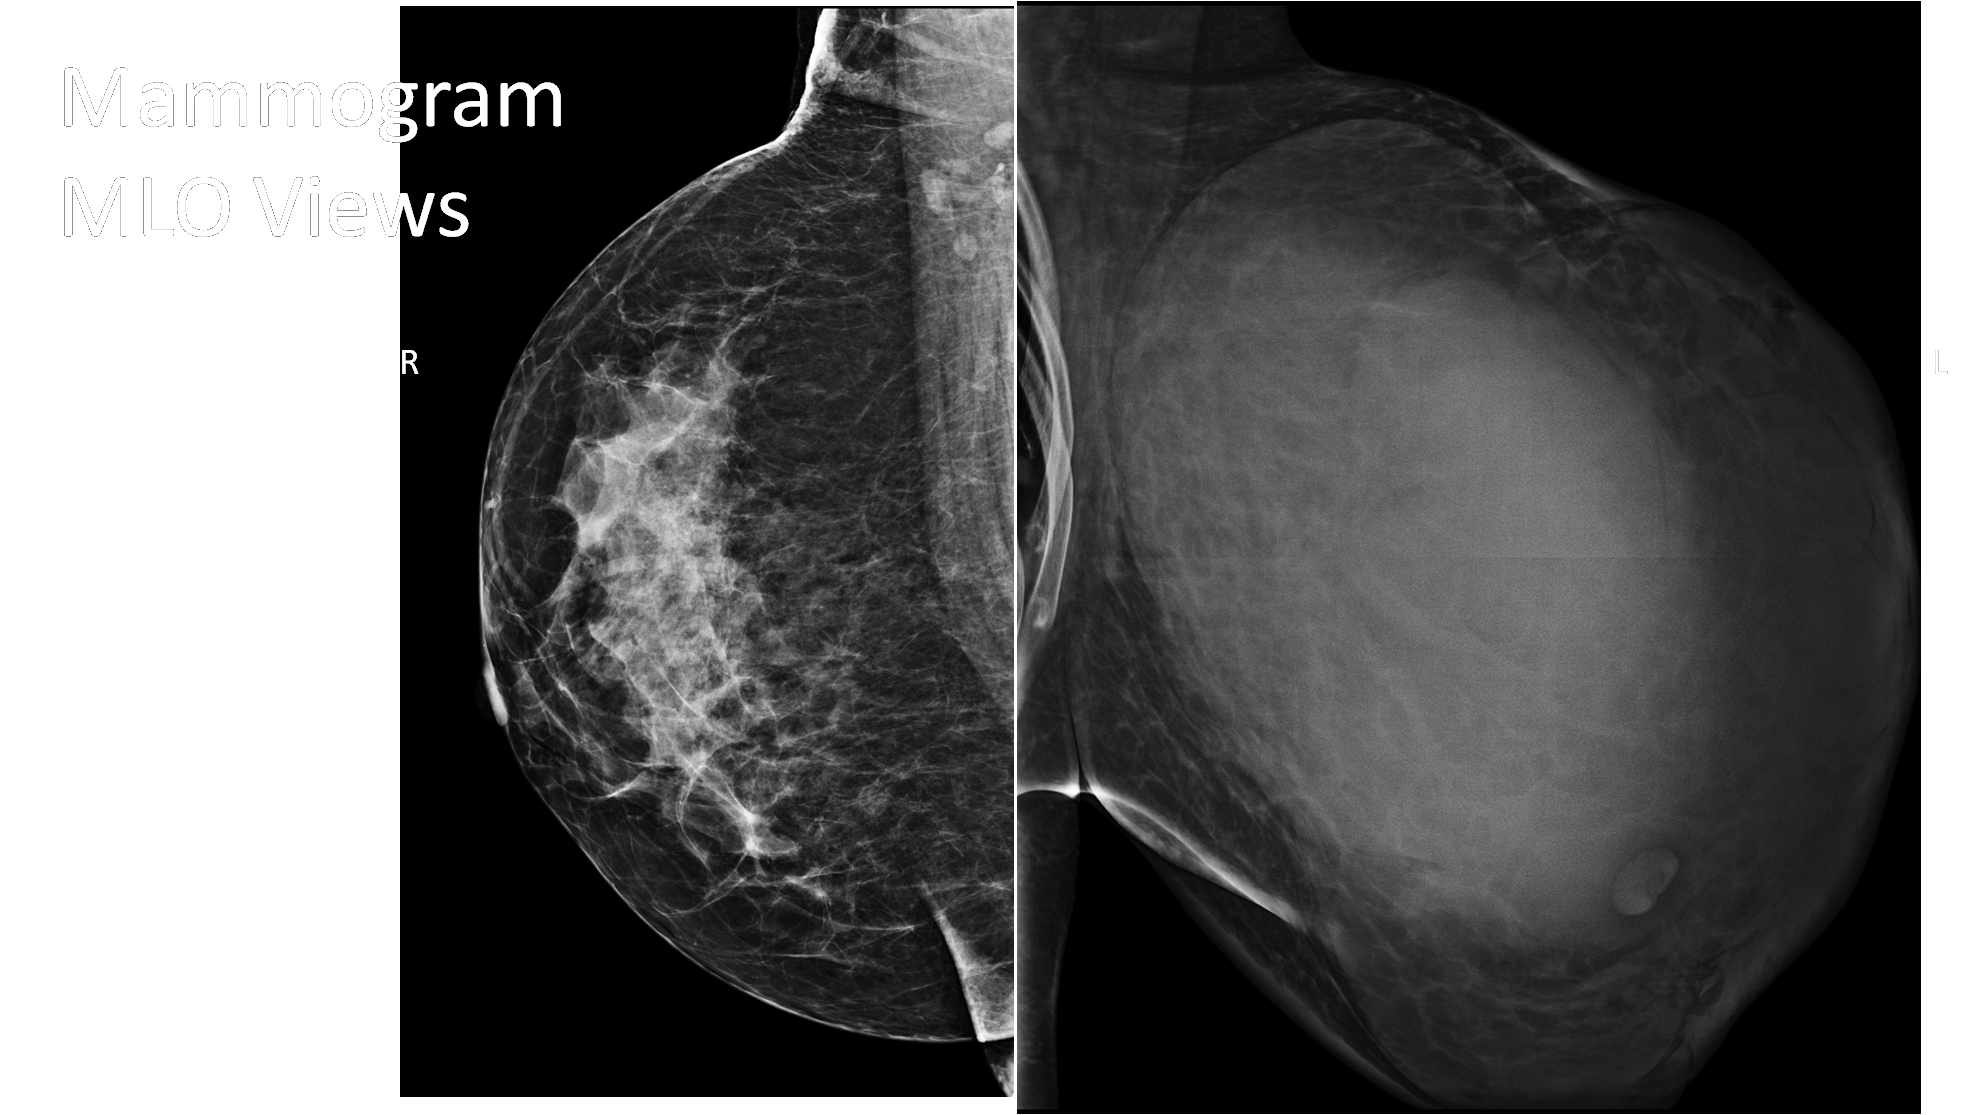

The left breast is enlarged and shows a large circumscribed mass of density similar to the fibroglandular parenchyma, occupying nearly entire left breast. There are no calcifications associated with the mass, however there is mild trabecular thickening and nipple retraction. The left breast mass is circumscribed , round to oval, mildly hypoechoic in appearance and shows multiple irregular fluid clefts (arrow). Excision specimen histology: Spindle cell tumour with infiltrative borders, increased stromal cellularity and moderate nuclear atypia. Areas of necrosis present. Mitotic count 5/10 HPF - Overall features are those of borderline phyllodes tumour